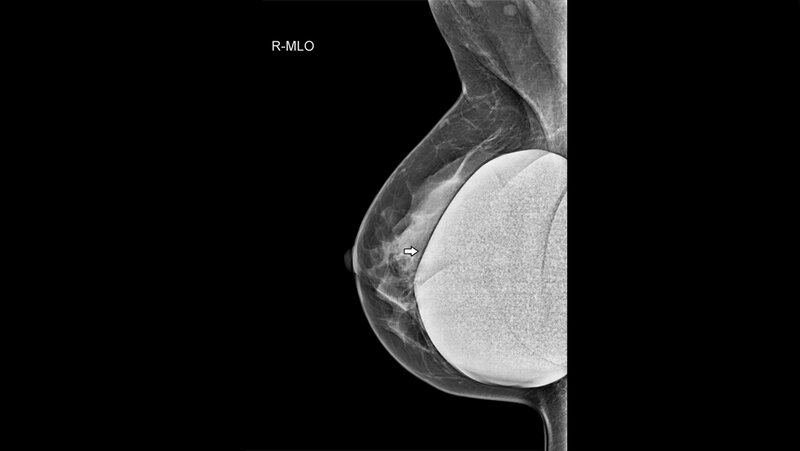

Anomalien und Normvarianten: noch einmal anders – alltägliche und nicht alltägliche Artefakte (Teil III)

Die Magnetfelder der MR-Tomografen können zu Interferenzen mit ferromagnetischem Material und gefährlichen Interaktionen führen. MR-Abteilungen sollten das Vorhandensein von metall- oder mineralhaltiger Kosmetik oder Haarprodukten ins Screening-Protokoll der Vorbereitung der Untersuchung aufnehmen. Neue Techniken können zur Artefaktreduktion führen. Algorithmen zur Artefaktsuppression stehen zur Verfügung.

Schlüsselwörter: Artefakte, Röntgen, Ultraschall, CT, MRT